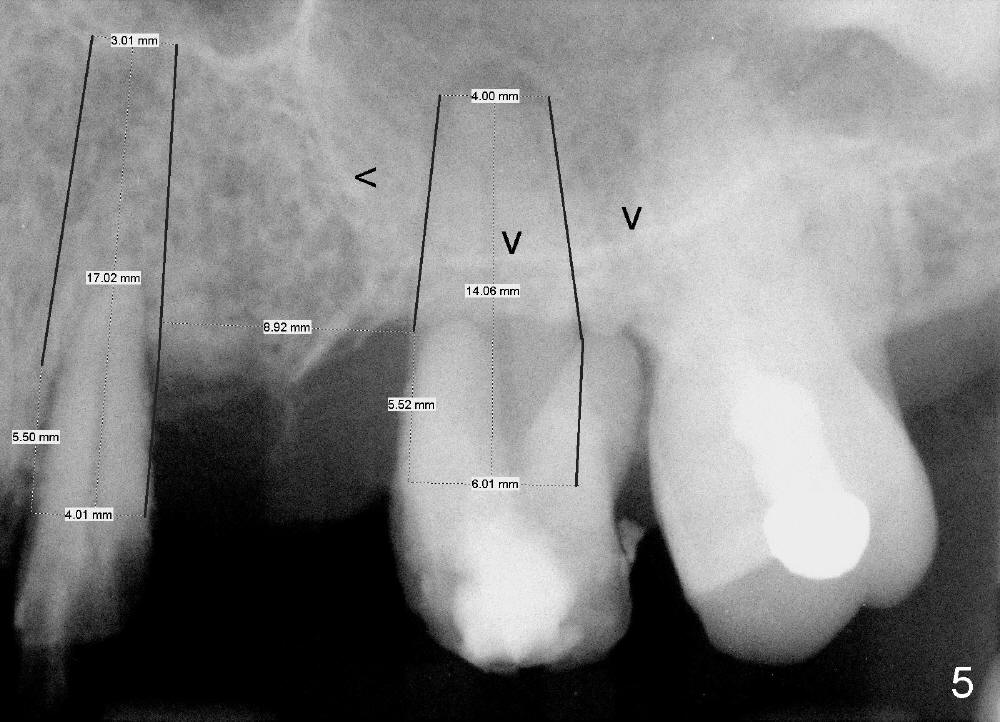

A 53-year-old lady has a failing bridge (Fig.1). There is severe bone loss around the buccal roots of #14 (*). Purulent discharge is from the gingival sulcus (Fig.2 <) with localized gingival erythema and edema (*). When the bridge is removed, the tooth #12 is found nonsalvageable (Fig.3,4). These two teeth are to be replaced by immediate implants (Fig.5). Although the sinus floor is low buccally (arrowheads), a 6x14 mm gingiva-level implant can be placed in the septum close to the palatal socket or in the palatal socket at the site of #14.

Initially the osteotomy is established with drill/reamers alternated with taps in the septum near the palatal socket. When a 4.5x14 mm tap (Fig.6 T; Fig.7: #14) is inserted, the sinus floor is perforated, but the sinus membrane is intact. When 7x14 mm tap is inserted, the sinus membrane is perforated in the buccal aspect of the osteotomy. The latter is repaired by placement of collagen dressing and then bone graft and membrane again (sandwich). The osteotomy is shifted to the palatal socket by using 5x14 and 6x14 mm taps. When the last tap is removed, the small area of the buccal aspect of the osteotomy is also found to be perforated, but the membrane is intact. When a 6x14 mm implant is placed (Fig.8), the coronal end is close to the middle of the socket (buccopalatally, due to angulation of the palatal socket).